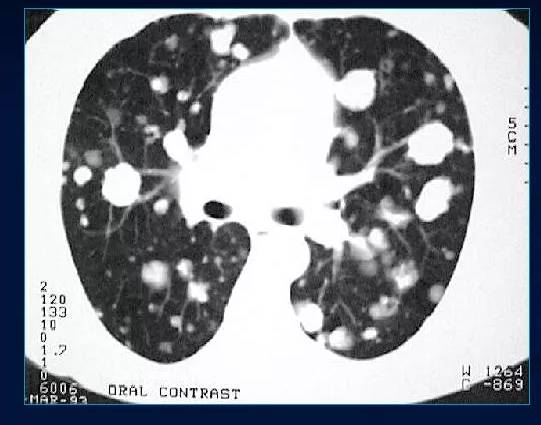

Структура легочных метастазов обычно соответствует морфологии и гистологии первичного очага и представляет собой узел, который распространяется от первоначального очага тонкой нитью. На рентгеновском снимке можно увидеть особенности патологического процесса — из центральной опухоли тянутся тонкие сплетения, которые прикрепляются к внутренним органам и тканям узловым фрагментом. Рентгенологическое изображение болезни графически напоминает рак, который распространяет свои щупальца по мере своего движения.

Метастазирование может иметь различные формы. Очаговые метастазы имеют менее агрессивное течение и распространяются гематогенным путем. При незначительном распространении очаговых метастазов можно ожидать благоприятного прогноза. Инфильтративные метастазы характеризуются распространением атипичных клеток по альвеолярному эпителию. На рентгене они выглядят как сетчатые затемнения и чаще распространяются лимфогенным путем, что повышает риск развития саркомы или меланомы. Смешанные метастазы объединяют признаки инфильтративного и очагового типов метастазирования.

При помощи компьютерной томографии можно определить путь и характер метастазов, а также выявить первичный очаг злокачественной опухоли. Обычно метастазы в легких свидетельствуют о четвертой стадии рака.

- Компьютерная томография (КТ) — это современный и доступный метод для определения вторичных раковых очагов, которые находятся глубоко в тканях плевры;